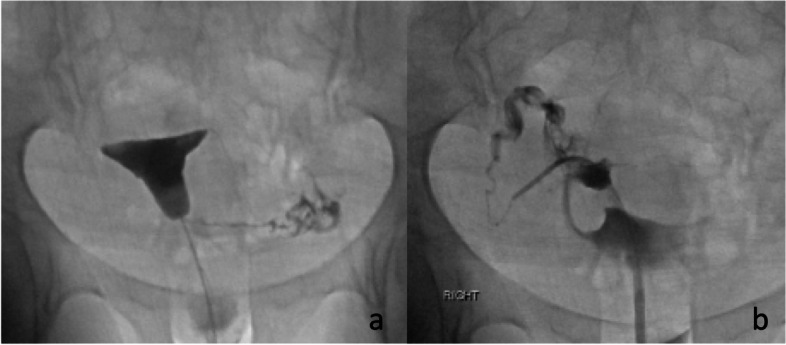

Fig. 7.

a shows filling of the left tube, but no filling on the right. In b the selective catheterization demonstrates a patent right tube